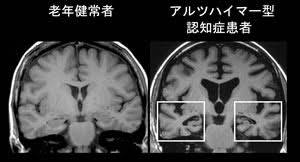

また、認知症の原因疾患であるアルツハイマー病は、次第に脳が委縮していく病気です。神経細胞が死滅して脳が小さくなるにつれ、知的機能が損なわれていくので、脳が小さいよりも大きい方が良いように思えるかもしれません。しかし、知能レベルの高い人が必ずしも大きな脳を持っているとは限りません。

また、認知症の原因疾患であるアルツハイマー病は、次第に脳が委縮していく病気です。神経細胞が死滅して脳が小さくなるにつれ、知的機能が損なわれていくので、脳が小さいよりも大きい方が良いように思えるかもしれません。しかし、知能レベルの高い人が必ずしも大きな脳を持っているとは限りません。